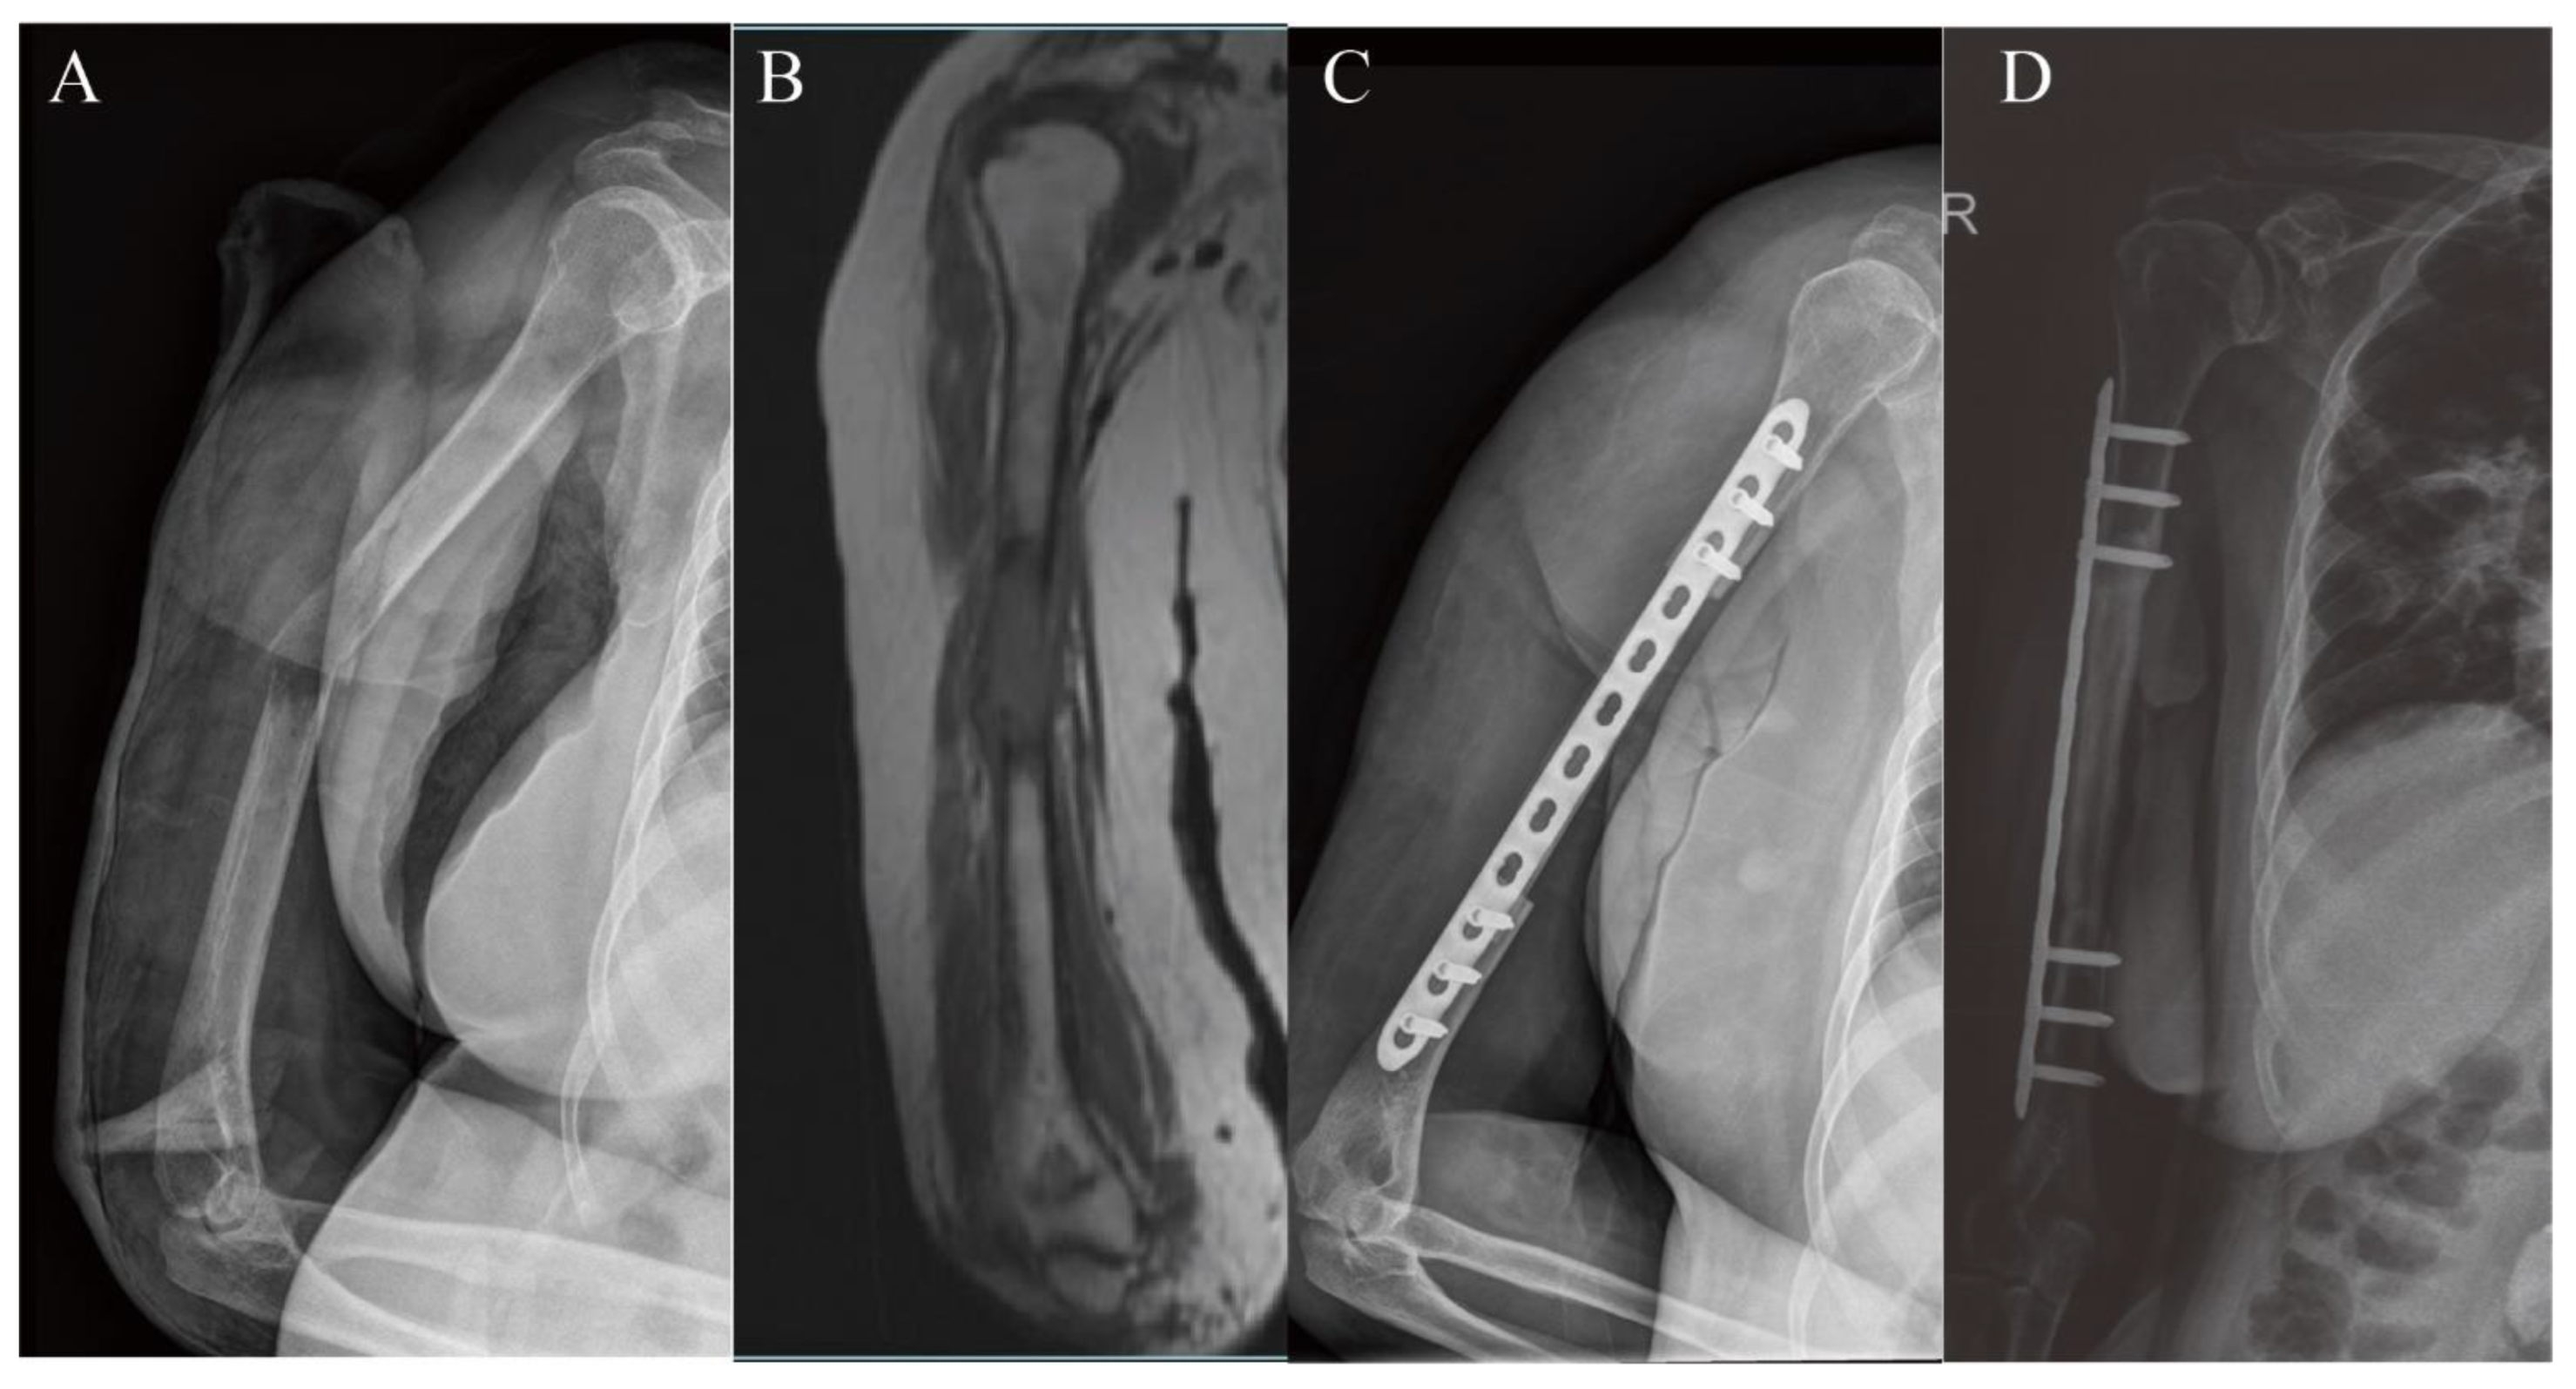

3.1. Upper Extremity Reconstruction Results

| 21 | 140 | 170 | No | allograft, double plate | 150 | 1000 | 124 | 9 | 29 | / |

| 22 | 110 | 130 | Yes | devitalized autograft, double plate | 495 | 1000 | 110 | 11 | 28 | / |

| 23 | 170 | 226 | Yes | devitalized autograft, double plate | 480 | 1450 | 38 | 10 | 19 | / |

| 24 | 130 | 150 | Yes | devitalized autograft, single plate | 420 | 1500 | 58 | 8 | 27 | Plate fracture |

| 25 | 150 | 170 | Yes | allograft, double plate | 330 | 1450 | 104 | / | 22 | Nonunion |

| 26 | 130 | 165 | Yes | devitalized autograft, double plate | 390 | 1450 | 64 | 6 | 30 | / |